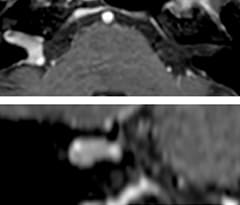

Using MultiBand SENSE allowed the staff to improve their diffusion quality. “Our diffusion sequence was already fast before, about 40 seconds. Now with Elition, it still lasts 40 seconds, but we improved the spatial resolution by 0.2 mm and use high b-values to be more sensitive to visualize changes related to acute stroke,” says Dr. Savatovsky. “We now also developed a high resolution DTI sequence (1.3 x 1.3 x 2 mm) that can be reformatted and takes 2 to 5 minutes depending on the coverage. We use it every time we have a doubt, or when we expect the diffusion to be abnormal but don’t see that on the fast sequence. We occasionally spot small ischemic infarctions that would not have been visible with the regular diffusion sequence.”

This is an example of acute ischemic stroke with distal occlusion of the right posterior cerebral artery. Note the improved visibility of the ischemic territory on the diffusion weighted image with high b-value. The 3D FLAIR shows a distal PCA occlusion. The fast SWIp depicts the thrombus on the isolated second echo image. The total scan time (including SmartBrain, preparations and a fast 3D T1w TSE Gd) is 8:00 minutes.